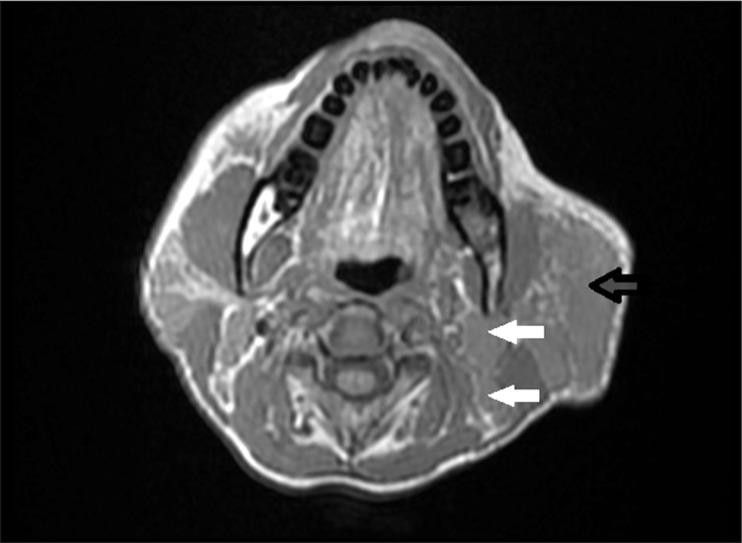

A middle-aged female patient presenting with a history of multiple chronic neck swellings was thoroughly evaluated by ultrasound (US), computed tomography (CT), and magnetic resonance imaging (MRI). The imaging findings included gross enlargement of the left parotid gland, a focal lesion in the right parotid gland, and cervical lymphadenopathy. These features correlated with histopathological findings, and the diagnosis of Kimura disease was made.

一名有多处慢性颈部肿胀病史的中年女性患者接受了超声(US)、计算机断层扫描(CT)和磁共振成像(MRI)的全面评估。影像学表现包括左侧腮腺明显肿大、右侧腮腺局灶性病变以及颈部淋巴结病。这些特征与组织病理学结果相关,从而做出了木村病的诊断。